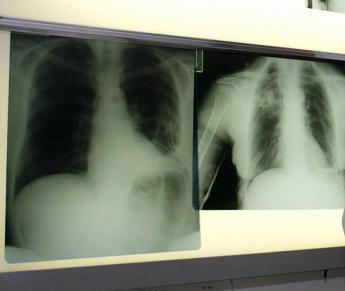

Nuova terapia per il cancro al polmone con mutazione Egfr in stadio precoce ha raggiunto una sopravvivenza senza precedenti nella malattia con l’88% dei pazienti vivo a cinque anni. I risultati positivi dello studio di fase III Adaura hanno mostrato che osimertinib, questo il nome del farmaco sviluppato da AstraZeneca, ha prodotto un miglioramento statisticamente significativo e clinicamente rilevante della sopravvivenza globale rispetto a placebo, nel trattamento adiuvante del carcinoma polmonare non a piccole cellule (Nsclc) in stadio precoce (IB, II e III A) che presenta mutazioni del recettore del fattore di crescita epidermico (Egfr), a seguito di resezione radicale. Sono questi i risultati illustrati oggi al Congresso annuale 2023 della Società americana di oncologia clinica (Asco) e pubblicati contemporaneamente sulla rivista The New England Journal of Medicine.

Osimertinib – si legge in una nota – ha ridotto il rischio di morte del 51% rispetto a placebo, sia nella popolazione dell’analisi primaria (stadio II-IIIA) che nella popolazione complessiva dello studio (Stadio IB-IIIA). Nella popolazione dell’analisi primaria, l'85% dei pazienti trattati con osimertinib è vivo a cinque anni rispetto al 73% dei pazienti trattati con placebo. Nella popolazione complessiva dello studio, l'88% dei pazienti trattati con osimertinib è vivo a cinque anni, rispetto al 78% di quelli trattati con placebo. La sopravvivenza globale mediana non è stata raggiunta sia nel braccio sperimentale che nel gruppo di controllo. I pazienti trattati con placebo che hanno sviluppato malattia metastatica hanno avuto l’opportunità di ricevere osimertinib come trattamento successivo. “Negli stadi precoci di malattia l’intento del trattamento è curativo – spiega Filippo de Marinis, direttore della Divisione di Oncologia Toracica dell’Istituto Europeo di Oncologia di Milano e Principal Investigator dello studio Adaura per l’Italia – La tradizionale chemioterapia non riesce a impattare in maniera significativa sulla diminuzione del rischio di recidiva di malattia locale o a distanza in percentuali superiori al 5%. Questi nuovi risultati dello studio Adaura dimostrano che quasi il 90% dei pazienti con tumore del polmone non a piccole cellule in stadio iniziale trattati con Osimertinib è vivo a 5 anni, con una riduzione del rischio di morte del 51%. La rilevanza di questi dati è senza precedenti: osimertinib è il primo inibitore tirosino-chinasico dell’Egfr a dimostrare un beneficio in sopravvivenza complessiva nel setting adiuvante nei pazienti con carcinoma polmonare non a piccole cellule Egfr mutato e sottoposti a chirurgia radicale. Risultati ancora più importanti se consideriamo che, nella malattia operabile, la sopravvivenza a 5 anni diminuisce dal 73% nello stadio IB fino al 41% nel IIIA. Il beneficio di osimertinib si estende a tutti i sottogruppi di pazienti. Infatti, negli stadi II-IIIA la sopravvivenza a 5 anni ha raggiunto l’85%. I risultati di Adaura rinforzano ulteriormente il beneficio di osimertinib quale standard di cura dopo la chirurgia nei pazienti con malattia in stadio precoce e positivi alla mutazione di Egfr”. “Nel 2022, in Italia, sono stati stimati quasi 44mila nuovi casi di carcinoma polmonare – afferma Saverio Cinieri, presidente Associazione italiana di oncologia medica (Aiom) -. Circa il 30% dei pazienti colpiti dalla forma non a piccole cellule riceve una diagnosi di malattia abbastanza precocemente da poter essere sottoposto a intervento chirurgico con intento radicale. Ciononostante, la recidiva è ancora frequente nel tumore agli stadi iniziali. Per questa ragione accogliamo positivamente i risultati dello studio Adaura, a conferma ulteriore dei grandi progressi che sta compiendo la ricerca in oncologia. È importante il ruolo rivestito da terapie mirate ed efficaci come osimertinib che portano di fatto a un miglioramento del percorso terapeutico del paziente e aumentano le possibilità di sopravvivenza a lungo termine”. “La chirurgia rimuove il carcinoma e taglia al livello macroscopico, ma non riesce a incidere su quello microscopico – sottolinea de Marinis -. Resta, cioè, un ‘microscopico invisibile’ rappresentato dalle micrometastasi, che si muovono nel sangue e nella linfa e incidono sulla ricaduta locale o a distanza della malattia nel tempo. Circa la metà dei pazienti con tumore di stadio I-II e tre quarti dei pazienti di stadio III presentano una recidiva a cinque anni dall’intervento. La disponibilità di osimertinib rende necessario eseguire, in tutti i pazienti operati, l’esame molecolare per verificare l’alterazione del gene Egfr, perché così possiamo individuare i pazienti candidabili alla terapia mirata”. Alla precedente analisi della sopravvivenza libera da malattia – prosegue la nota – tutti i pazienti avevano completato o interrotto il trattamento. La sicurezza e tollerabilità di osimertinib al follow-up esteso è risultata in linea con il profilo consolidato e con le analisi precedenti, senza nuove segnalazioni di sicurezza. Gli eventi avversi di Grado ≥3 per tutte le cause si sono verificati nel 23% dei pazienti nel braccio con osimertinib rispetto al 14% in quello con placebo. Il tumore del polmone è la causa principale di morte per cancro tra gli uomini e le donne, e rappresenta circa un quinto di tutti i decessi per cancro. Il tumore del polmone si suddivide in Nsclc e tumore del polmone a piccole cellule. Si stima che ogni anno, a livello globale – conclude la nota – 2,2 milioni di persone ricevano una diagnosi di tumore al polmone, di cui l’80-85% classificato come Nsclc, la tipologia più comune. La maggior parte dei pazienti con Nsclc presenta una diagnosi di malattia avanzata, mentre circa il 25-30% presenta malattia resecabile alla diagnosi. Le diagnosi di cancro al polmone in fase iniziale vengono spesso rilevate solo quando il cancro viene identificato mediante indagini radiologiche effettuate per altre condizioni non correlate. La maggior parte dei pazienti con tumore resecabile sviluppa una recidiva nonostante la resezione completa del tumore e la chemioterapia adiuvante. Inoltre, solo il 73% dei pazienti in Stadio IB e il 56-65% di quelli in Stadio II sopravvive a cinque anni. La percentuale scende al 41% nei pazienti in Stadio IIIA, il che dimostra una elevata necessità medica insoddisfatta. —salutewebinfo@adnkronos.com (Web Info)